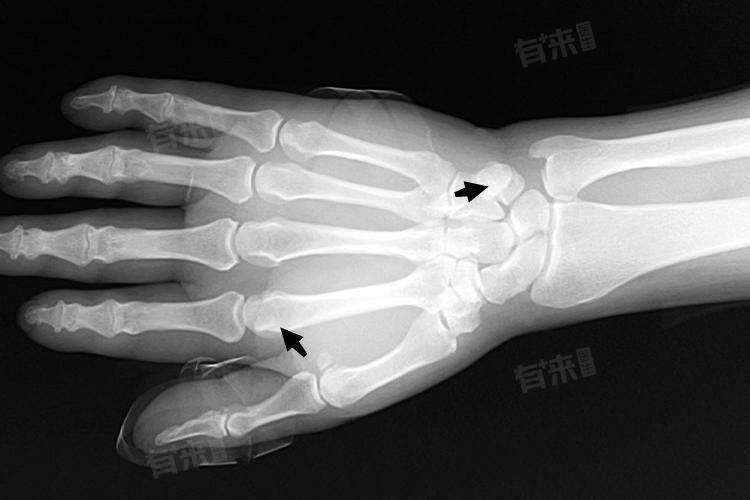

籽骨的出现通常提示一定的骨龄阶段,但具体时间因个体差异有所不同,一般籽骨出现时骨龄大致在10岁到13岁左右。

籽骨的出现提示着身体生长发育进入了一个新的阶段。在这个阶段,家长和孩子应更加关注身体的变化,保持良好的生活习惯和饮食习惯,以促进身体的健康成长。同时医生在进行骨龄评估时,也会结合籽骨的出现情况以及其他骨骼特征来综合判断孩子的生长发育状况。如果籽骨出现时间明显早于或晚于正常范围,可能需要进一步检查,以确定是否存在生长发育异常的情况。